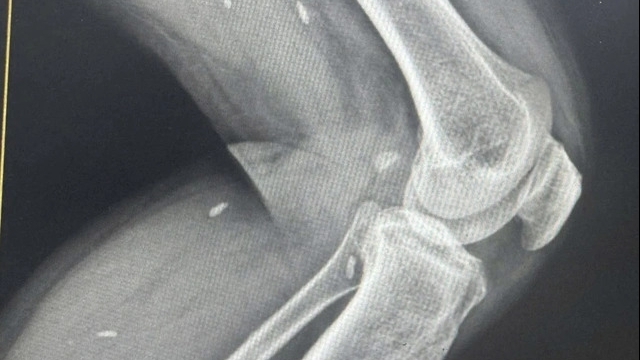

Người đàn ông này được chuyển đến Bệnh viện Thần kinh Tam Cửu, Quảng Đông, Trung Quốc, để được điều trị chuyên sâu hơn. Tại đây, bác sĩ Diêm Học Cường cho biết ông đã cho bệnh nhân chụp CT não để xác định nguyên nhân. Hình ảnh phim chụp cho thấy bên trong não của bệnh nhân có sán nhái (một loài thuộc họ sán dây có tên khoa học là Spirometra Mansoni) chiều dài lên đến 10 cm.

Bác sĩ Diêm cho rằng đây chính là nguyên nhân chính gây nên những cơn co giật của ông Trương. Nó đã ký sinh trong não lâu năm nên một số tổ chức mô xung quanh có những nốt u nhỏ li ti chứa trứng sán. Ông Trương được mổ gắp sán và lọc bỏ các ụ trứng đề phòng tái phát về sau.